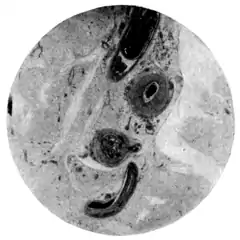

| Fig. 1.—Schistosomum japonicim in vessels of mesentery. (Microphotograph: Dr. Henderson.) |

Fig. 2.—Eggs of Schistosomum japonicim embedded in walls of appendix vermiformia. (Microphotograph: Dr. Kerr.) |

In Catto's case the ova were found chiefly in the mucous and submucous coats of the intestinal tract from cæcum to anus, more especially in the rectum and appendix. They were also found in the liver, in the gall-bladder, in the pancreas, in the mesenteric glands, and in the fibrous coat of the larger mesenteric vessels. In the liver they were very plentiful, lying singly or in clusters embedded in the hypertrophied connective tissue. The female schistosomum probably has a special means of extruding her eggs through the walls of the blood-vessels; the further distribution of the eggs being effected by the lymph-stream. Where the ova accumulate they provoke a small-cell infiltration, which gives place later to fibrous tissue.

The ova are discharged in the fæces of the vertebrate host. In this way they get carried to water, where the ciliated miracidium escapes. In 1913 Miyairi and Suzuki traced the ciliated miracidium into a fresh-water mollusc, Katayama nosophora (Fig. 143), wherein, after shedding its cilia, it becomes a sporocyst (Fig. 144, a), in which ultimately numbers of fork-tailed cercariæ are developed (Fig. 144, b). On maturity the cercariæ escape into the water and, opportunity presenting, penetrate the skin of some appropriate vertebrate (man, cat, dog, mouse, etc.), in whom they attain sexual maturity. These observations have been confirmed by Leiper.